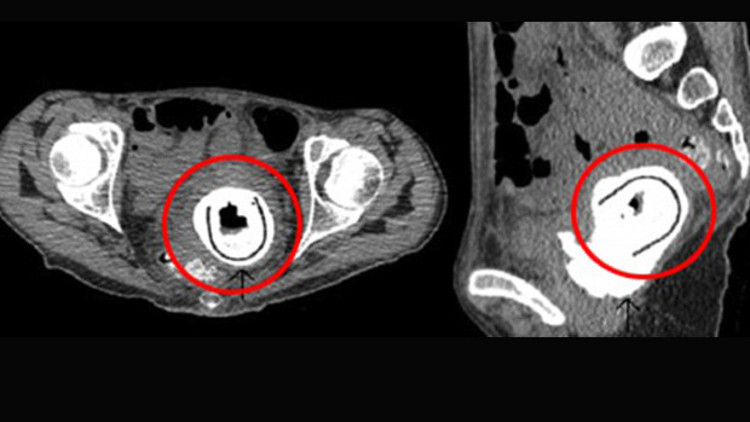

Herhangi bir zihinsel rahatsızlığı bulunmadığı gözlenen 38 yaşındaki kadının açıklaması ise “10 yıl önce partnerimle birlikte bu oyuncağı kullandım. O sırada alkolün etkisindeydim ve oyuncağı vajinamdan çıkarıp çıkarmadığımı hatırlamıyorum” şeklinde oldu.

Ameliyat sonrası “vezikovajinal fistül” (idrarın vajinaya sızması) ve “obstrüktif üropati” (idrarın böbreklere geri dönmesi) hastalıklarına yakalandığı anlaşılan kadın tedavi altına alındı.

Doktorlara göre sinir hücrelerinin bu kadar yoğun olarak bulunduğu vajina gibi bir bölgede yabancı bir cismin varlığını hissetmemek oldukça nadir görülen bir durum.